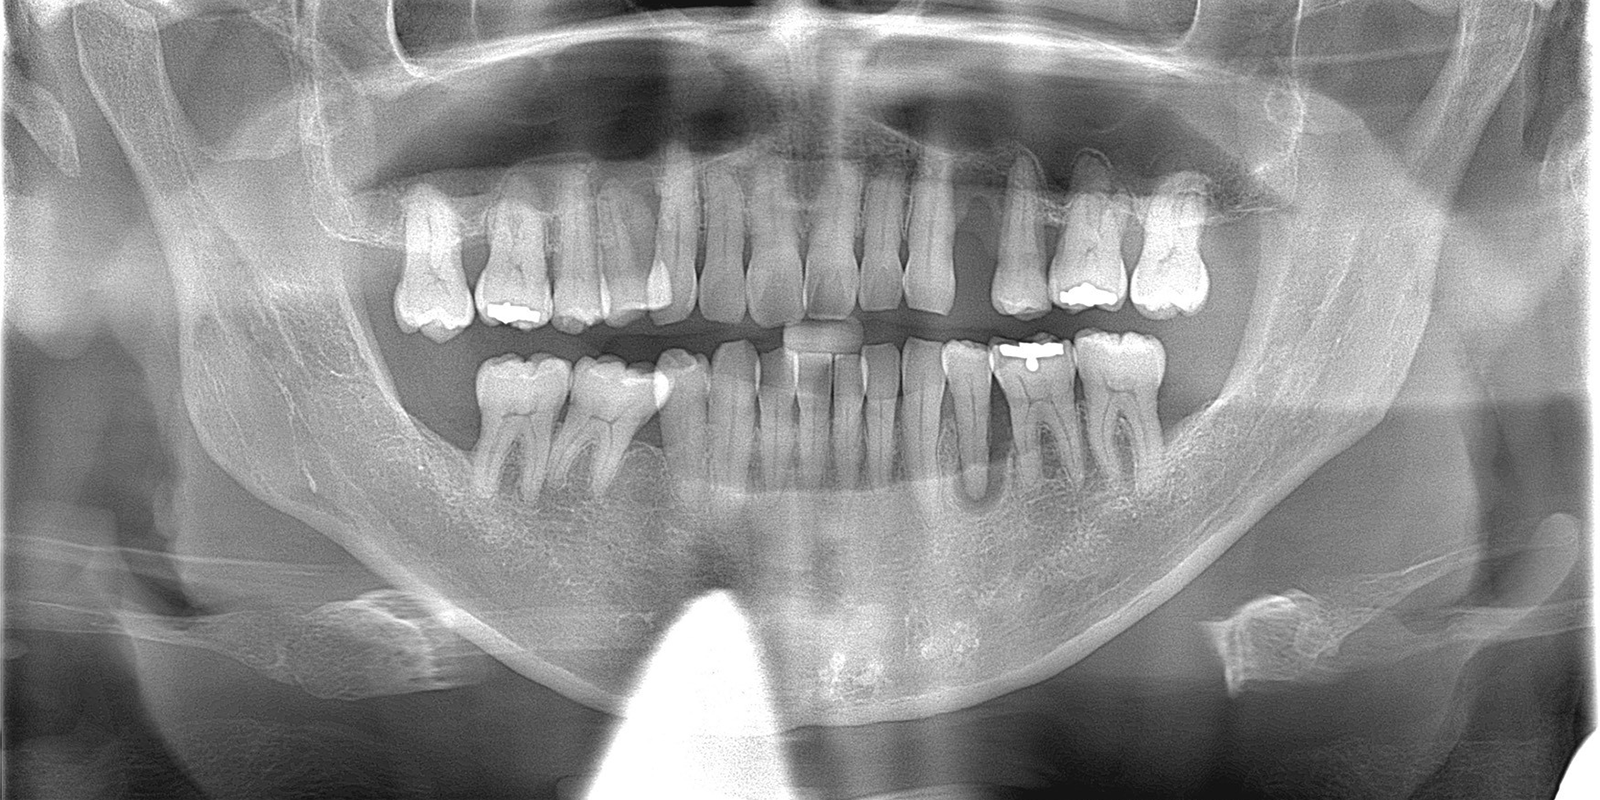

本日は根管治療と歯周病治療を併用した症例についてご紹介いたします。

上顎の両側4番目の歯が歯周病により、自然に脱落、もう一本は抜け落ちる寸前です。

レントゲンでみると右下5番目(実際は左下5)の歯根の先端が黒く抜けています。この状態は、重度歯周病と根尖性歯周炎(根が膿んでる)が混在しており非常に予後が悪いとされています。

| 診断名 | 重度歯周病、欠損歯、根尖性歯周炎 |

術前術後のレントゲンでの比較です。明らかに黒く骨欠損が著しかったところが、白く写り良質な骨が復活しているのがわかります。本症例では、骨補填剤は使っていないため全て自家骨での復活です。上顎両側4番目の歯は今後、インプラント治療を行っていく予定です。